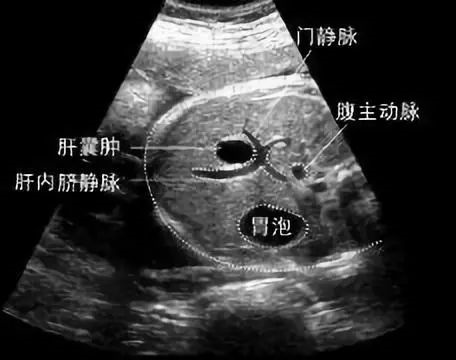

通俗地说 , 肝囊肿就是肝脏上的水泡 , 一般不和外面相通 , 位置较浅或个头大的 , 可突出来 , 使肝表面变得不光滑 。

囊肿大小不一 , 小的如针尖 , 大的像个椰子 。

但是多数就是几毫米到几厘米大 , 可以是一个 , 也可以是好几个 , 内部结构可以是‘单间’ , 也可是‘套间’ , 囊内还会有液体 , 所以看起来就像个水泡 。